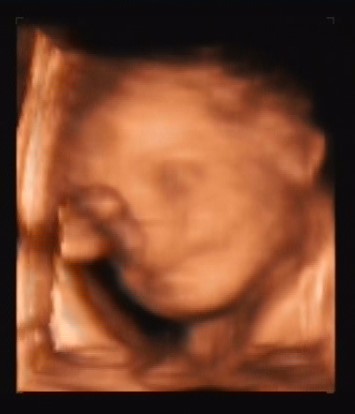

Baba fekvése: az enyém még naponta vagy 3x megfordul, határozottan érzem! És leginkább keresztben szokott megállni!

Tuti hogy még nagyon ráérnek befordulni! A barátnőmnek a 38. héten már mondta a doki hogy faros úgyhogy készüljön a császárra és az utsó 2 hétben gyönyörűen megfordult és másfél óra

alatt meg is született!! Szóval nem kell parázni, ráérünk a végén!!